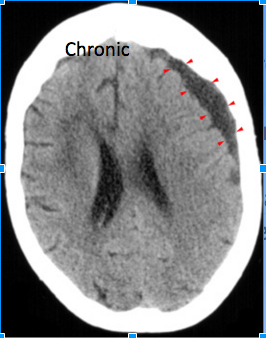

Chronic Subdural hematoma: Whats importnat to notice in this CT?

Crescent shaped chronic subdural hematoma (arrowheads)

Notice

the low attenuation due to reabsorbtion of the hemorrhage over time.